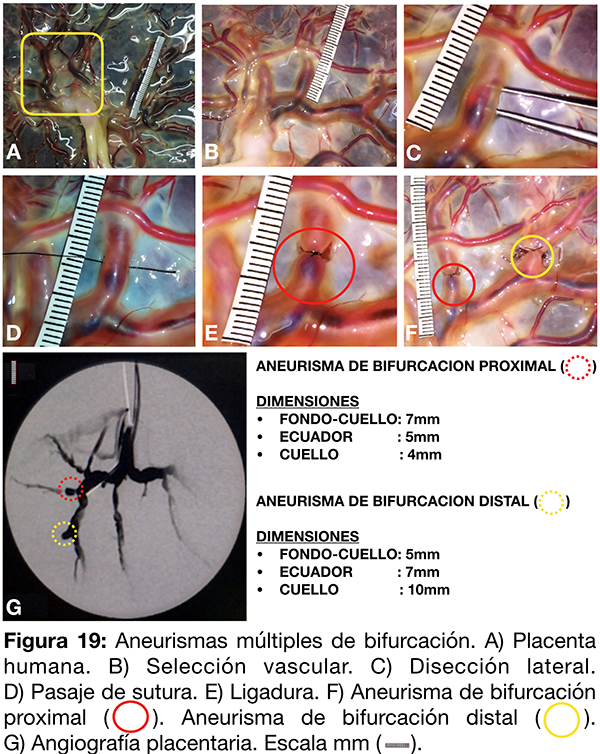

II-Aneurismas múltiples de bifurcación: Generación y control angiográfico.

Se selecciona un territorio arterial de la placenta para la generación de múltiples aneurismas de bifurcación (fig. 19 A-B). Tras disecar la membrana amniótica con micro tijera, se disecan en forma filosa las caras laterales vasculares y se prosigue con la región infra vascular (fig. 19 C). Se practican ligaduras con nylon 8-0 conformando los aneurismas de bifurcación proximal y distal (fig. 19 D-E-F). Finalmente se cateterizan los vasos arteriales mediante catéter guía 6F y se inyecta contraste diluido al 70% (fig. 19 G).